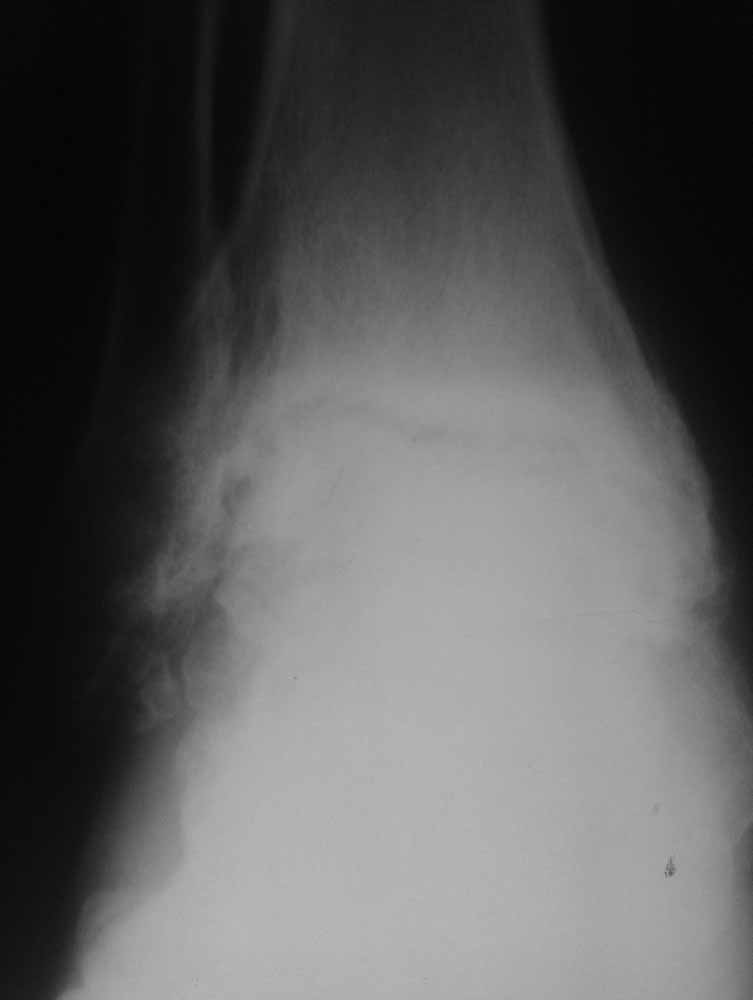

Склоняемся к мысли, что все таки Charcot's Joint.

Планируем артродез стержнем правого голеностопа + аппарат на левый голеностоп.

Вложение не в текстовом формате было извлечено…

Имя     : правый профиль.jpg

Тип     : image/jpg

Размер  : 27321 байтов

Описание: отсутствует

Url     : http://weborto.net:8080/pipermail/ortho/attachments/20111203/f37772b8/attachment-0006.jpg